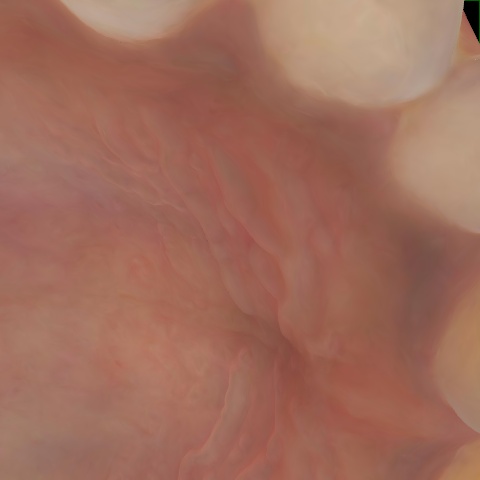

NHD39174

Overview

Annotated as "Good"